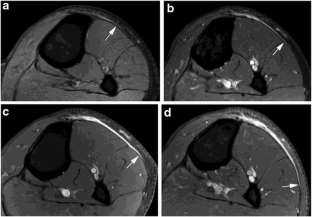

Recurrence of a soft tissue sarcoma typically manifests as a round or oval mass at imaging, and recurrent high-grade soft tissue sarcomas generally enlarge relatively rapidly. We present a case of high-grade undifferentiated pleomorphic sarcoma in the calf of a 48-year-old male that recurred as a thin, curvilinear “tail” of enhancing tissue at magnetic resonance imaging (MRI), with extremely indolent growth over a 7-year period. The unusual imaging finding of a slowly enlarging “tail” should not be dismissed as postoperative changes, even for a high-grade soft tissue sarcoma.

Fig. 1